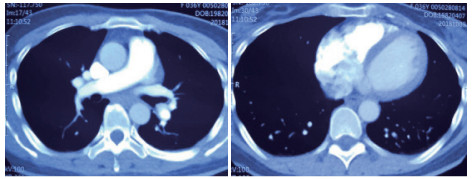

例2 72岁,男性。主因“活动后气短3 d,加重伴有晕厥1次”住院。既往体健,否认制动史及手术史。入院查体:神志清楚,体温36℃,血压120/70 mmHg,脉搏110次/min,呼吸22次/min,脉氧93%(安静,空气氧),轻度乏氧征。双肺呼吸音清,未闻及干湿性啰音。心率110次/min,心律齐,P2 > A2,心界无扩大,无杂音。腹软,无压痛,肠鸣音正常,双下肢无浮肿。神经系统查体未见异常。血气分析(安静,空气氧)提示pH 7.457,PaCO2 26.7 mmHg,PaO2 74.0 mmHg,SaO2 95.5%;D-Dimer 13 743 ng/ml;FDP 175.060 μg/mL,FBG 1.990 g/L;PLT:224 G/L;cTnI 0.04 ng/mL,BNP 666 pg /mL;ALT 15 U/L,AST 27 U/L,CREA 103.3 mmol/L,血Na+、K+、Cl-:正常范围;UCG提示:右心增大,肺动脉主干增宽(28 mm),三尖瓣反流(中-重度),反流面积11.5 cm2,TI法估计SPAP为50 mmHg、左室舒末内径38 mm、左心功能稍减低E波/A波= 60/40 cm/s,未见节段性室壁运动障碍;双下肢静脉超声提示右侧股总、股深、股浅、腘静脉及双侧小腿肌间静脉丛血栓形成。心电图(图 5所示)提示窦性心动过速;CTPA提示双肺主干明确充盈缺损(图 6所示)。入院诊断:急性PE(中高危)。给予低分子肝素重叠华法令抗凝治疗。D-Dimer由入院时13 743 ng/mL分别降至第2天10 000 ng/mL,第3天9 000 ng/mL和第四天的5 000 ng/mL。住院第4天开始出现纳差、恶心未吐,复查心电图提示窦性心动过速,SⅠQⅢTⅢ,胸导T波加深(如图 7所示)。入院第5天床上排便后出现呼吸急促,储氧面罩吸氧(Flow 10 L/min)维持氧合78%(当天INR 2.02),15 min后出现血压、心率下降至消失,心外按压始终无自主呼吸及心律恢复,因家属放弃系统溶栓治疗,抢救2 h无效宣告患者临床死亡。回顾入院后连续复查的心电图提示右心负荷有逐渐加重及胸前导联缺血加重的倾向;UCG同样证实右心室内径呈进行性增大的趋势(分别为入院时的右心房31 mm×47 mm、第2天28 mm×40 mm和第4天的54 mm×60 mm)。

| 图 6 入院时CTPA提示双肺主干明确充盈缺损 |